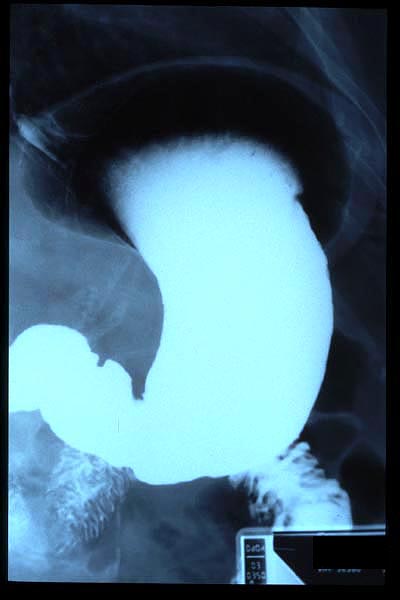

Hernia de hiato gigante.